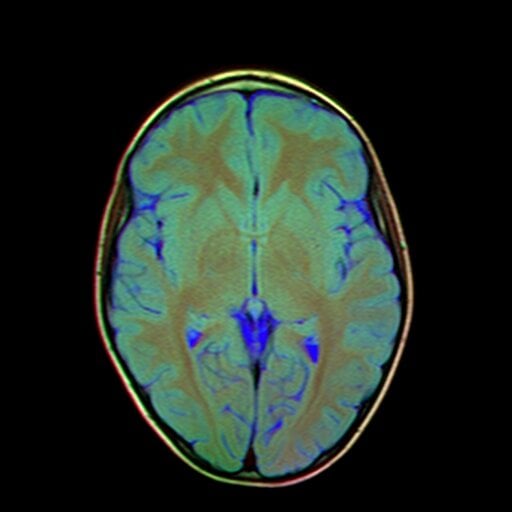

Magnetic Resonance Imaging of the brain is essential for understanding structural and functional changes within the central nervous system. Marris Medical offers high-quality imaging designed to detect subtle abnormalities that may impact cognitive or neurological health. With fast, comfortable scan experiences and highly trained specialists, we ensure precise evaluations for every patient.